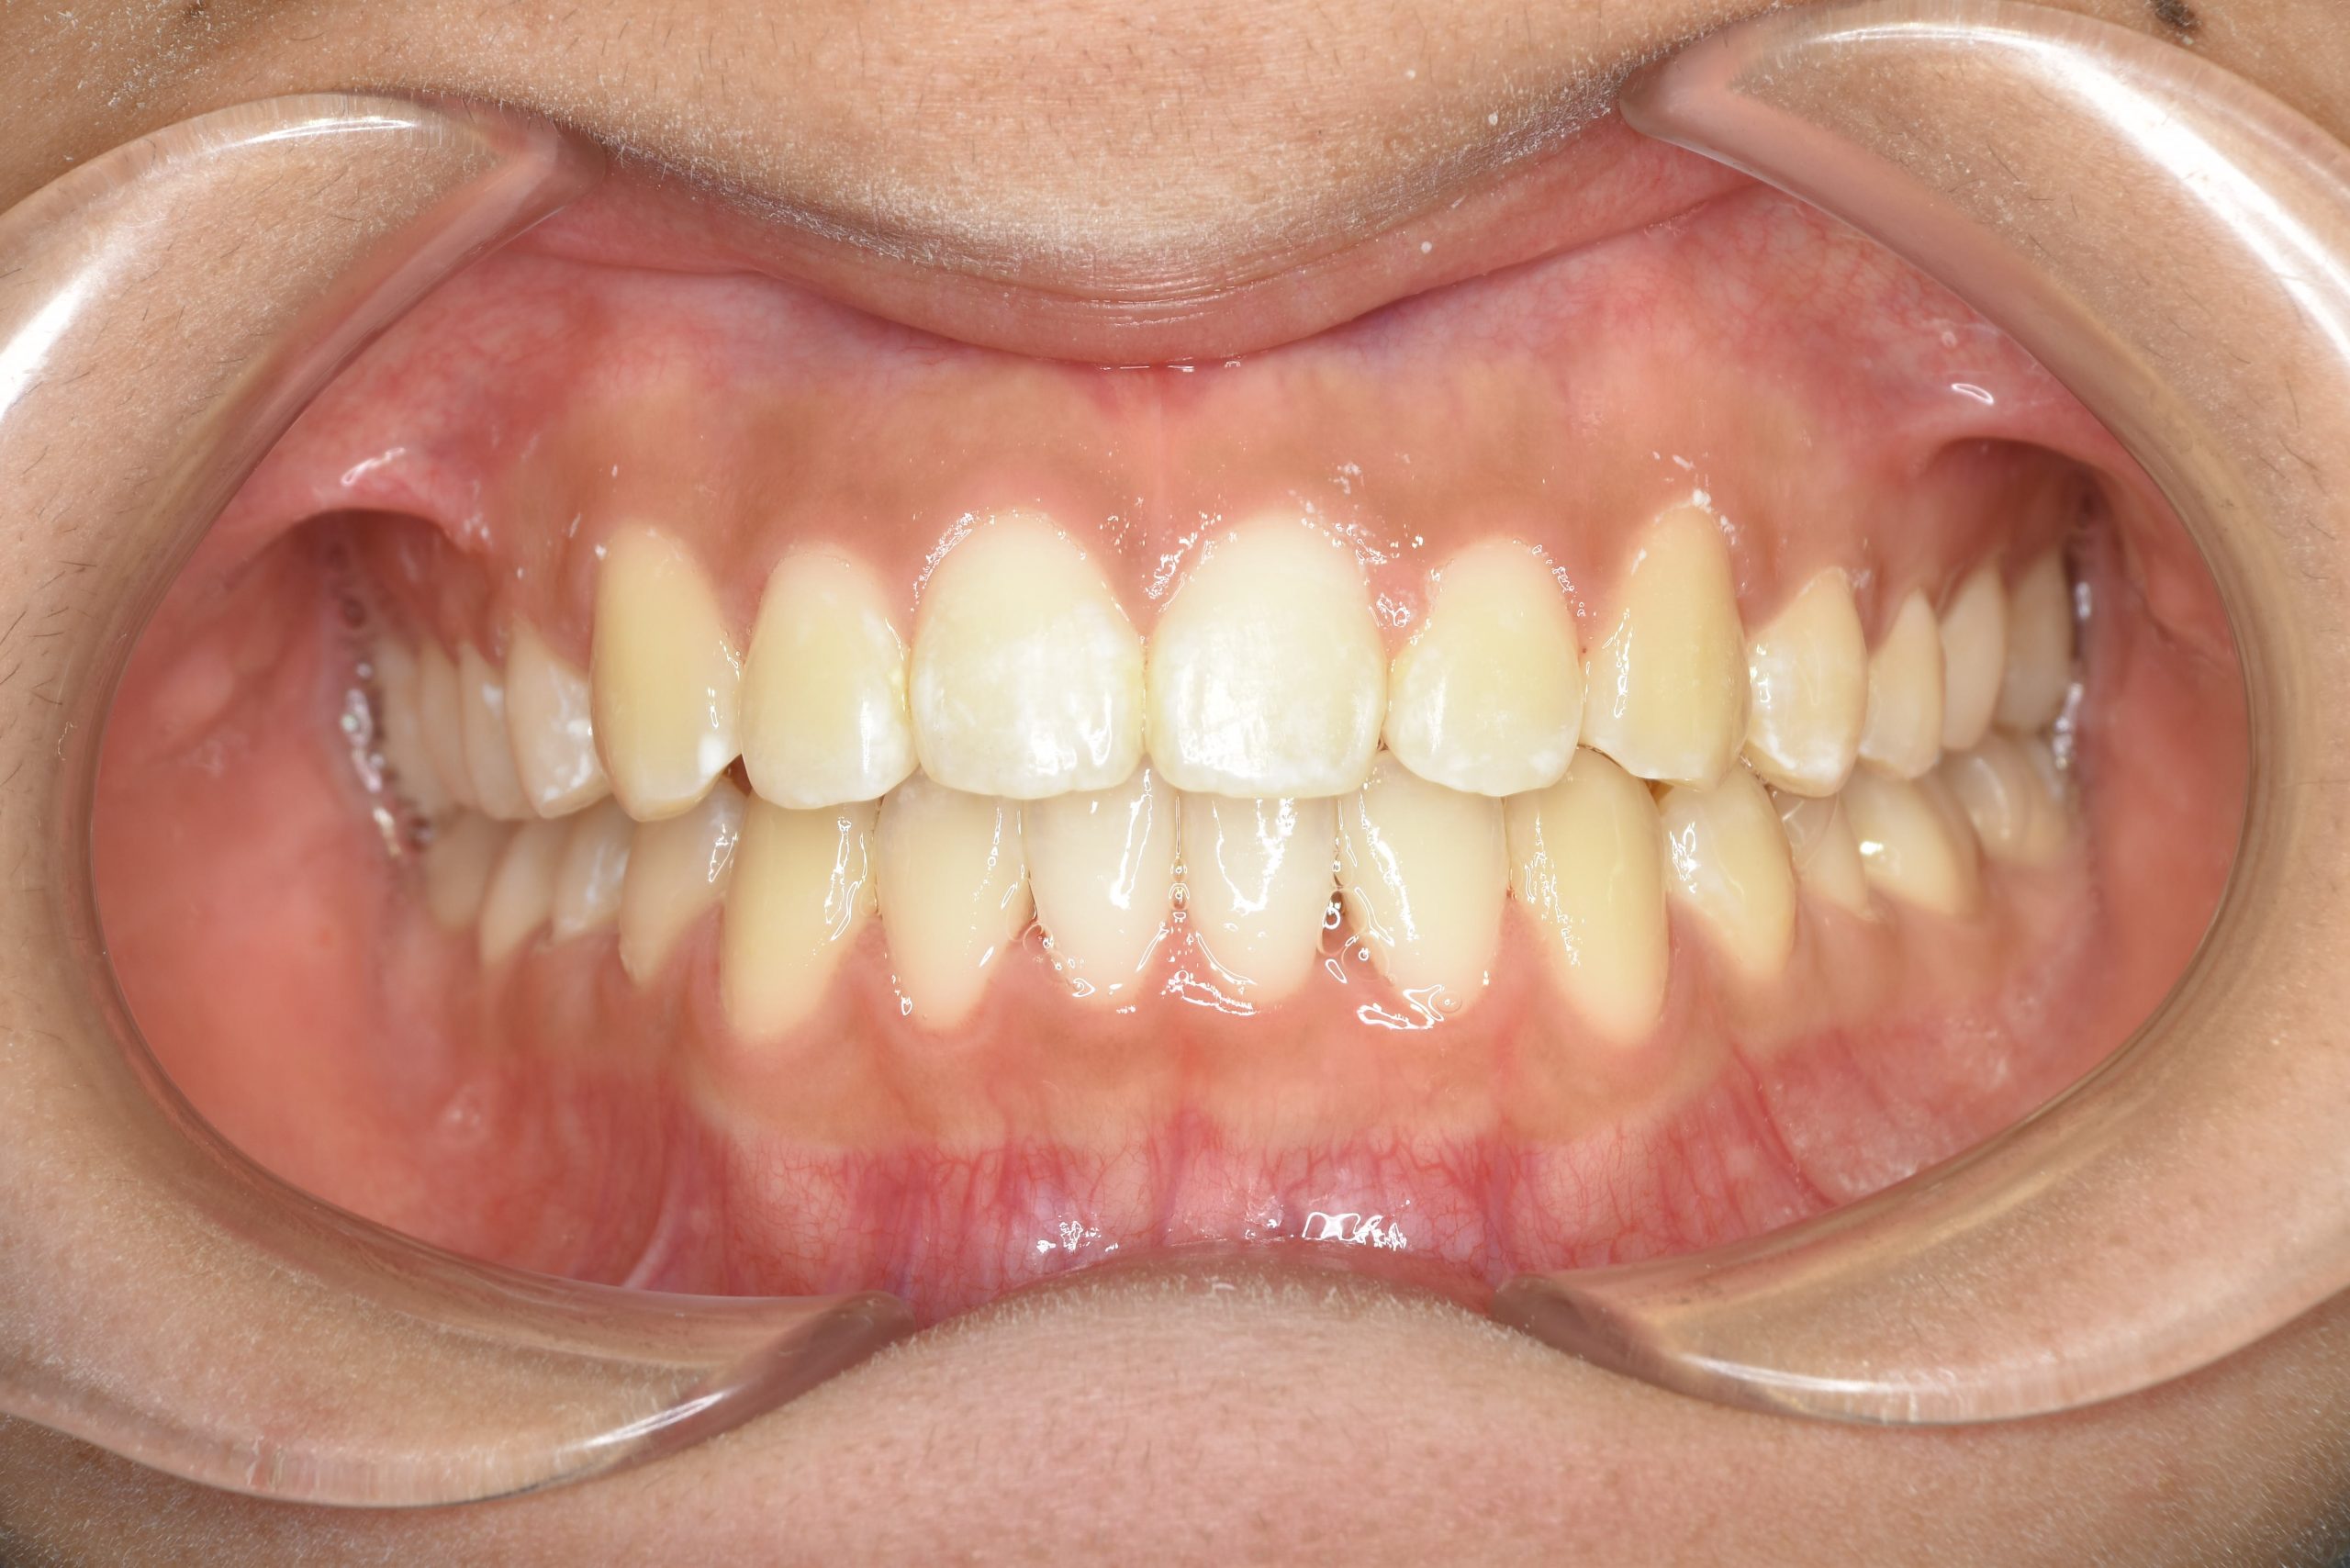

ビフォー

アフター

主訴 前歯の歯並び

施術内容 成人矯正1期治療

治癒期間 1年2か月間

費用 954,800円(税込)